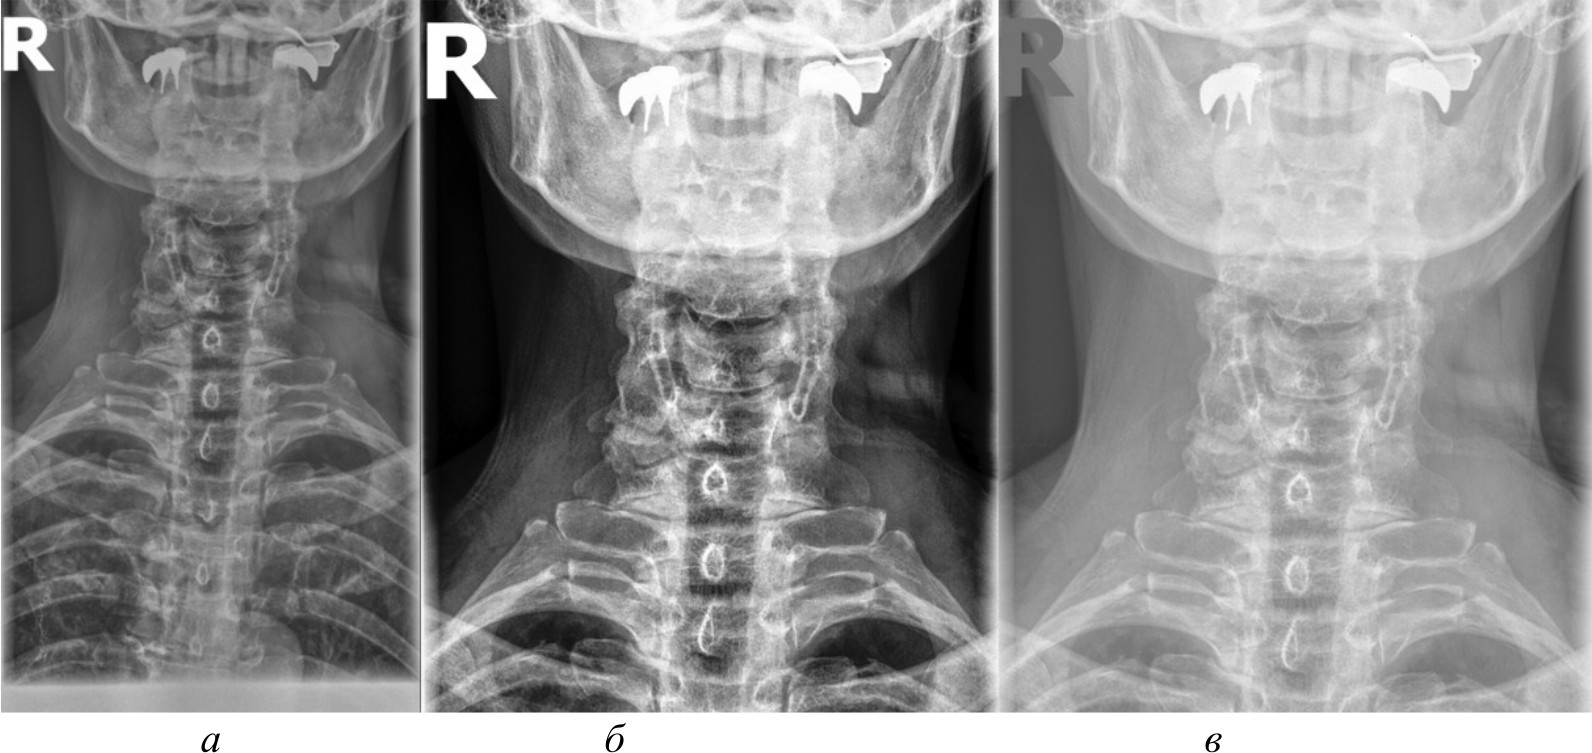

Для создания эталонного набора изображений рентгеновские снимки в формате DICOM были загружены в специализированное программное обеспечение для медицинской визуализации. DICOM является стандартным форматом для медицинских изображений, который позволяет сохранять изображение с высоким качеством и дополнительной информацией об исследовании. Однако для дальнейшей обработки и анализа эти DICOM-файлы конвертируются в более распространенные графические форматы. Специализированное программное обеспечение сохраняет их в формате PNG. На рис. 2, а представлено изображение, полученное в результате работы в специализированном программном обеспечении.

- базовое отображение Python. Изображения загружены в Python и отображены при помощи библиотеки Pillow без применения каких-либо дополнительных преобразований. Данный метод представлен на рис. 2, б;

- медианный фильтр. Для сглаживания шумов и артефактов на изображениях к базовому отображению Python применен медианный фильтр из библиотеки OpenCV. Размер окна фильтра был подобран эмпирически. Данный метод обработки представлен на рис. 2, в;

Рис. 2. Изображение, полученное при помощи специализированного программного обеспечения (а), метод базового отображения в Python (б), метод базового отображения Python с применением медианного фильтра (в)